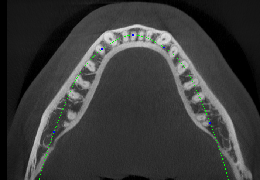

View X-Ray CT & MRI Scans Fast and Easily

Designed for surgeons, Pro Surgical 3D makes it easy to view patient scans quickly. Pro Surgical 3D facilitates the optimal 3D treatment and assessment workflows based on X-ray CT and MRI scans – and best of all, it’s FREE!

High-quality and fast 3D reconstruction and 3D rendering

Performs 3D reconstruction and volume rendering.

Multi-planar slicing.

Instant and interactive surface extraction and export to STL and PLY formats.